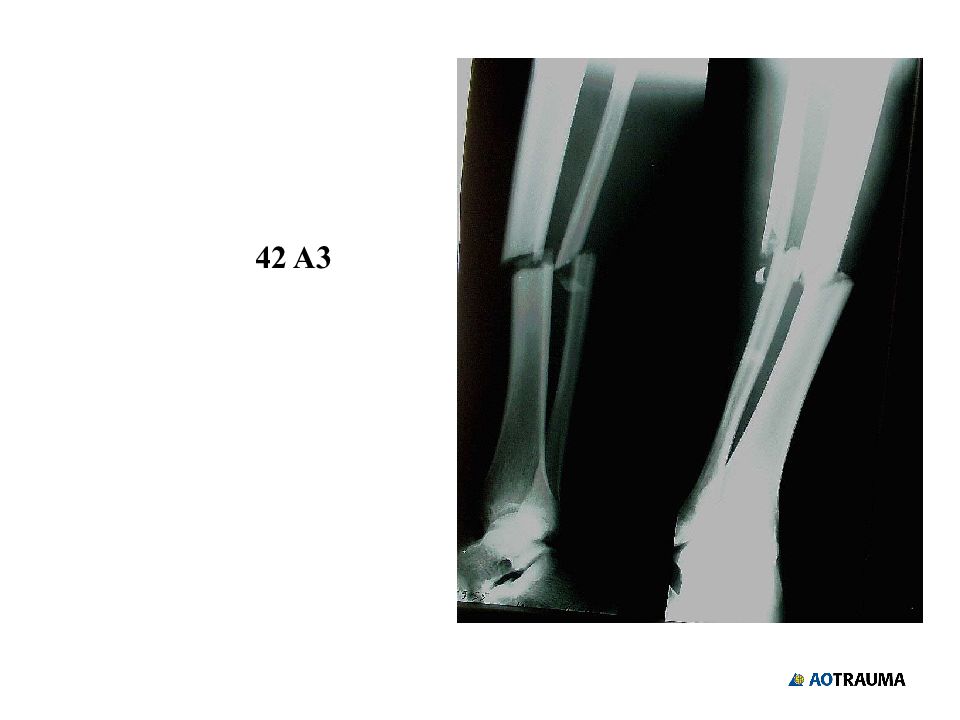

Слайд 30

42 A 3